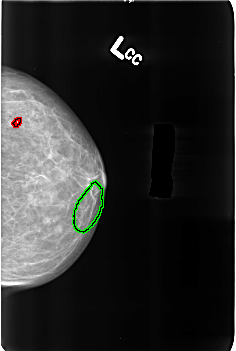

B_3164_1.LEFT_CC

FILE: B_3164_1.LEFT_CC.OVERLAY

TOTAL_ABNORMALITIES 2

ABNORMALITY 1

LESION_TYPE CALCIFICATION TYPE COARSE DISTRIBUTION N/A

ASSESSMENT 2

SUBTLETY 5

PATHOLOGY BENIGN_WITHOUT_CALLBACK

TOTAL_OUTLINES 1

BOUNDARY

ABNORMALITY 2

LESION_TYPE CALCIFICATION TYPE VASCULAR DISTRIBUTION N/A